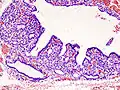

Hyperthyroidism is one of the most common endocrine conditions affecting older domesticated housecats. In the United States, up to 10% of cats over ten years old have hyperthyroidism.[60] The disease has become significantly more common since the first reports of feline hyperthyroidism in the 1970s. The most common cause of hyperthyroidism in cats is the presence of benign tumors called adenomas. 98% of cases are caused by the presence of an adenoma,[61] but the reason these cats develop such tumors continues to be studied.

The most common presenting symptoms are: rapid weight loss, tachycardia (rapid heart rate), vomiting, diarrhea, increased consumption of fluids (polydipsia), increased appetite (polyphagia), and increased urine production (polyuria). Other symptoms include hyperactivity, possible aggression, an unkempt appearance, and large, thick claws. Heart murmurs and a gallop rhythm can develop due to secondary hypertrophic cardiomyopathy. About 70% of affected cats also have enlarged thyroid glands (goiter). 10% of cats exhibit "apathetic hyperthyroidism", which is characterized by anorexia and lethargy.[62]